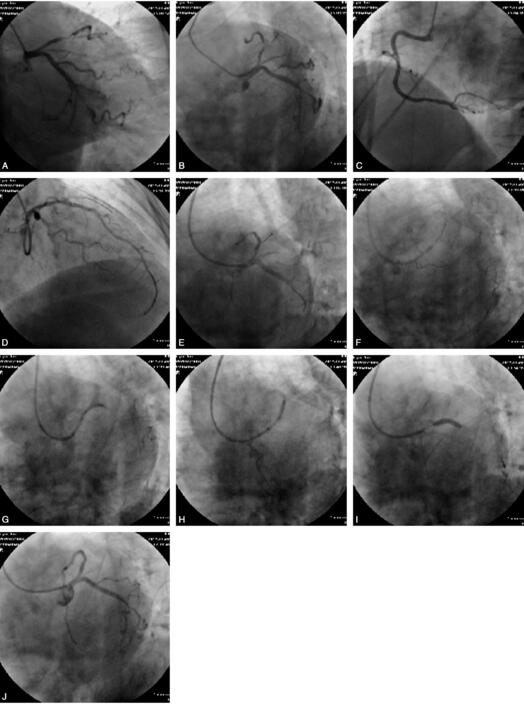

患者,女性,82岁,以“间断胸闷、胸痛3个月余,加重2天”入院。患者于入院前3个月开始出现胸闷、胸痛,呈压迫感,夜间多发,曾住院药物保守治疗,病情好转。入院2天前感胸痛加重,行冠脉CT检查示:前降支近段第一对角支开口处90%狭窄,对角支开口90%狭窄,LCX及RCA无狭窄。既往:有“高血压、2型糖尿病”病史10余年,给予降压药物及胰岛素治疗,血压及血糖控制均不理想。入院查体:血压150/90mmHg心率72次/分,律齐,各瓣膜无杂音。实验室检查未见异常。入院心电图显示:V1~V4导联T波低平。诊断:冠心病,不稳定型心绞痛。给予冠心病药物强化治疗,病情稳定1周后行冠脉造影检查。CAG结果:左主干直径约1cm,LAD近段95%以上狭窄,第一对角支开口次全闭;LCX远端可见50%局限性狭窄,RCA未见狭窄。根据造影结果:以EBU3.5指引导管置左冠口,送BMW导丝至前降支远端,另一BMW导丝于第一对角支予以保护,以APEX1.5mm×15mm及微创2.0mm×15mm球囊于前降支狭窄处扩张,压力为8atm×8s,然后置入EXCEL 2.5mm×18mm支架于前降支近段狭窄压力最大为18atm,造影提示TIMI 3级,第一对角支开口闭塞;预交换导丝,回撤对角支导丝时,患者突然出现胸痛,同时血压下降至80/40mmHg,心电监测示:心率40次/分,回放造影提示指引导管深插入前降支导致前降支支架近段、左主干远端及回旋之开口夹层,同时出现大量血栓,回旋支近段也可见大量血栓形成,血流缓慢,立即送BMW导丝至回旋支远端,给予多巴胺2ml、阿托品1mg、吗啡2mg静推,5分钟后再次造影血栓负荷仍较重,给冠脉内推注尿激酶10μg;10分钟后再次于冠脉内推注替罗非班5ml、加大多巴胺用量,并送美敦力2.5mm×20mm球囊于前降支支架近段以12atm压力扩张,分别于回旋支、前降支置入支架,行Crush术,此后胸痛缓解,生命体征平稳,观察5分钟后撤出导丝及指引导管,送入ICU进一步观察治疗。此后复查心脏B超未见异常,恢复良好出院。手术经过见图5。

图5 A~C.前降支近段及第一对角支开口均95%以上狭窄;D.前降支置入支架后;E~J.大量血栓形成、LAD及LCX近段支架置入过程